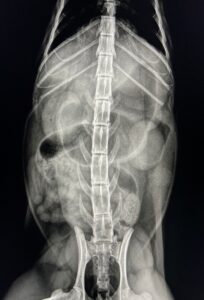

超音波検査:虹彩・毛様体を起源とする腫瘤病変を疑う。下顎および内側咽頭後リンパ節への明らかな転移所見なし。

画像②:超音波検査にて腫瘤病変を確認